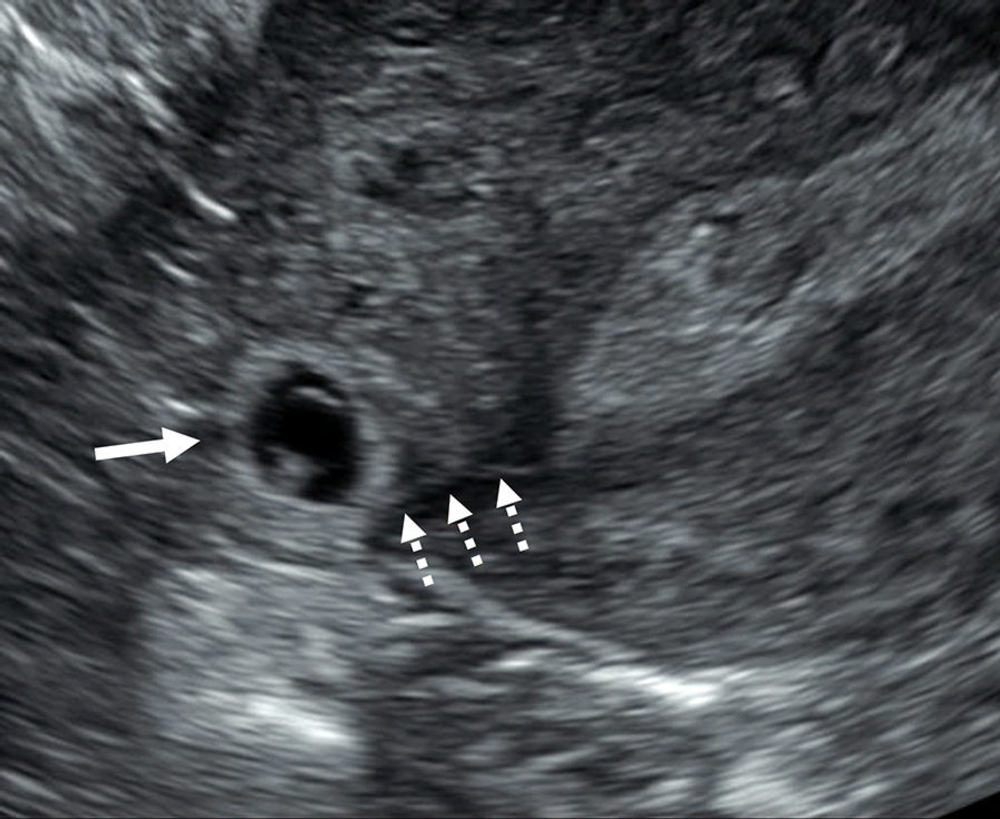

Figure 11. Interstitial line sign. Transvaginal transverse grayscale US image in a 33-year-old pregnant patient shows a right interstitial ectopic pregnancy (EP) (solid arrow) at 6 weeks 0 days. In addition to the characteristic sonographic findings of an interstitial EP shown in Figure 10, there is a thin echogenic line (dotted arrows) representing the interstitial segment of the tube. This line connects the endometrium to the ectopic gestational sac and is called the interstitial line sign.